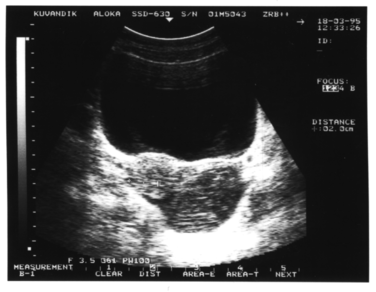

Рисунок 1. Однокамерный вариант гидро-сальпингса.

. Однокамерный вариант. В пространстве между одним из яичников и маткой (вдоль боковой стенки матки), то есть в одной из параметральных областей, выявляется жидкостное образование правильной вытянутой формы со значительным преобладанием продольного размера над поперечным. При этом конфигурация патологического очага может быть овальной (рис.1), веретенообразной или S-образной. Структура жидкого содержимого однородная. Матка, эндометрий и яичники не изменены. На стороне поражения почти всегда лоцируется неизмененный яичник. Оптимальные условия для визуализации патологического очага создаются при поперечном обзорном сканировании с использованием способа дозированной компрессии передней брюшной стенки УЗ-датчиком (желательно секторным).Как правило, этот вариант воспаления маточных труб встречается у молодых женщин и часто обнаруживается при первичном обращении к гинекологу.